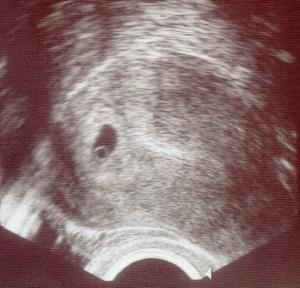

Hämaturie wenn Blut den Urin färbt.

Wenn eine Blasenentzündung ausgeschlossen wurde kann die Blutung auch aus der Gebärmutter stammen. Auch wenn eine solche Blutung ein Warnzeichen ist und ein Hinweis für Fehlgeburtsbestrebungen wird eine solche Blutung nicht zwangsläufig in einer Fehlgeburt enden. Die Farbe zeigt an ob eine Schwangerschaft besteht oder nicht. Da hier regelmäßig der Urin mit Teststreifen kontrolluert wird kann ich sagen dass in diesen 9 Monaten nichts an Blut im Urin gefunden wurde. Es sei aber fast schon normal dass man in der Schwangerschaft Blut im Urin habe und hätte meist nix zu bedeuten. Zur Klärung wird Ihre Urinprobe im Labor untersucht. Weiß jemand ob das richtig ist. Harnwegsinfekte wie Blasenentzündung und Harnröhrenentzündung sind häufige Ursachen für Blut im Urin. Häufig handelt es sich um eine Harnwegsinfektion doch auch andere teils schwerwiegende Ursachen können dafür verantwortlich sein.

Ein Jahr später wurde ich mit meinem Sohn schwanger. So in der 7 -8 ssw hatte ich sogar bei Blut im Urin das war aber nicht so schlimm hat der Artz gemeint und in der Mitte der SS so in der 20 ssw hatte ich das wieder hab das später in Mutterpass gesehen der Arzt hat hichts dazu gesagtIch würde sagen wenn das schlimm bzw. Die Ursache ist häufig ein bakterieller Befall der Harnwege. Hinzu kommt dass in der Schwangerschaft die sogenannte glomeruläre Filtrationsrate der Niere erhöht ist wodurch unter anderem mehr Blutzucker Glukose an den Urin abgegeben wird ein geeigneter Nährboden für Bakterien. Die Farbe zeigt an ob eine Schwangerschaft besteht oder nicht. Weiß jemand ob das richtig ist. Blut im Urin in der Frühschwangerschaft.